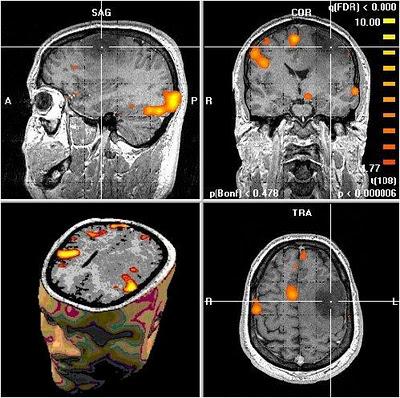

Ashley N. Gearhardt, MS, M. Phil., De la Universidad de Yale, New Haven, Connecticut, y sus colegas hicieron un experimento en el que tomaban medidas de las señales emitidas por el cerebro (a través de resonancias magnéticas) en respuesta a la ingesta de un alimento muy sabroso batido de chocolate frente a una solución de control de mal gusto, y también ante el consumo de otro batido de chocolate frente a una solución sin sabor.

Los participantes con una alta adicción a la comida demostraron una mayor actividad en el cortex prefrontal dorsolateral y el caudado antes de la ingesta del batido de chocolate y la reducción de la activación en el cortex orbitofrontal lateral durante el consumo en si de dicho alimento sabroso, frente a los que no tienen dicha adicción los cuales tuvieron una activación menor de dichas zonas antes de la ingesta.